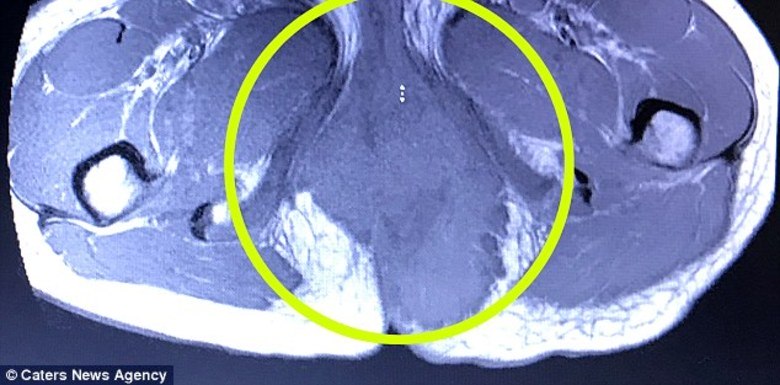

No entanto, o caroço continuou a crescer até que ele era do tamanho de um melão. Foi em uma cirurgia com o intuito de remover um abcesso períneo que os médicos descobriram uma grande massa em suas nádegas. Ao passar por uma tomografia computadorizada, chegaram ao real diagnóstico: rabdomiossarcoma alveolar — uma forma de câncer de tecidos moles.

A jovem passou por seis meses de radioterapia para tratar a doença. Agora, o tumor desapareceu completamente e Elie está 90% recuperada.